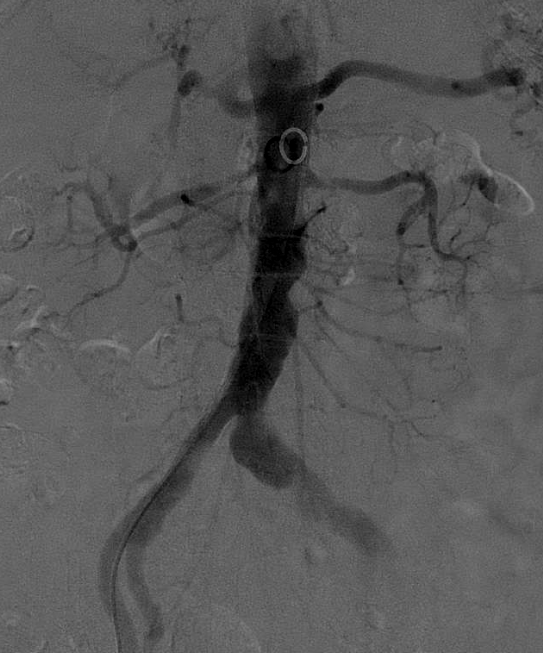

局麻后穿刺右股总动脉并置入7F血管鞘。腹主动脉造影示:腹主动脉管腔不光滑,左侧髂总动脉管腔增粗,双侧肾动脉管腔重度狭窄,右侧可见副肾动脉,左侧副肾动脉显示不清。

全身肝素化,7F RDC配合4F Sim1导管选入右肾动脉,(4mm-20mm)Aviator Plus球囊预扩,植入(6mm-18mm)Palmaz Blue支架。

7F RDC配合4F Sim1导管选入左肾动脉,(4mm-20mm)Aviator Plus球囊尝试送入左肾动脉困难,更换(2mm-15mm)Gateway球囊后成功送入左肾动脉并完成预扩,植入(5mm-18mm)Palmaz Blue支架。

复查造影:支架位置及形态满意,未见明显残余狭窄,双侧肾动脉及分支血流通畅。